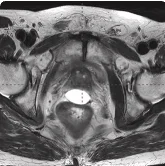

161 cc prostate post-MRI showing BioProtect Balloon Spacer, prostate, and rectum.

Post-MRI

Image courtesy of Dr. Shawn Zimberg, Radiation Oncologist.